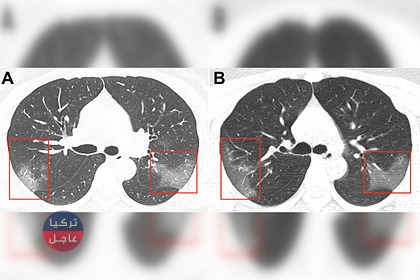

بدأت الأطباء الصينيون بتضييق الحلقة حول فيروس كورونا القاتل، وتناقلت وسائل إعلامية صورا لرئتين مصابتين بفيروس كورونا 2019-nCoV.

وذلك نقلن عن أطباء صينيين مختصين بتشخيص الفيروس وتم نشر نتائج التصوير الطبقي المحوري لمريضة تبلغ من العمر 33 عاما في مجلة Radiology.

وعلى أساس الخصائص الوبائية، والأعراض السريرية ونتائج التصوير الطبقي المحوري، تم تشخيص إصابتها بالالتهاب الرئوي 2019-nCoV.

وبعد ثلاثة أيام من العلاج، زادت المنطقة المصابة من الرئتين (الصورة ب) – في الصور تبدو معتمة.